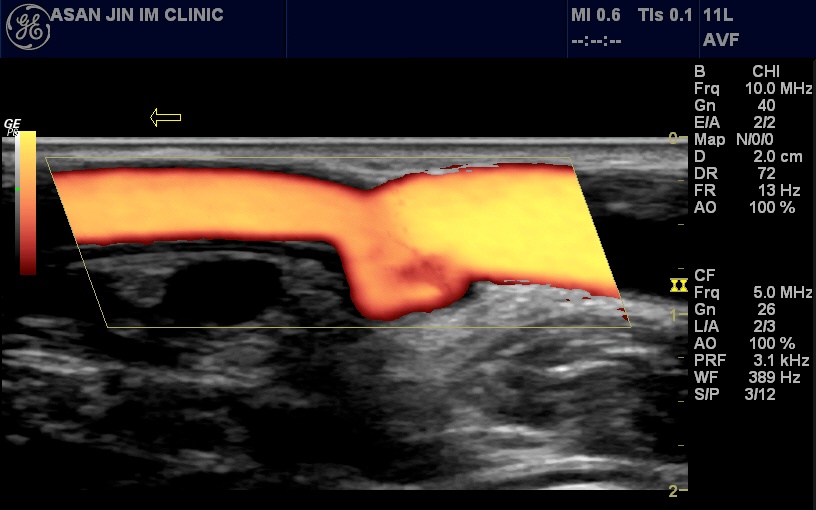

(평가항목: 인력은 전문인력 비율, 의사 및 간호사 1인당 투석 건수, 장비는 필수 장비(B형 간염 환자용 혈액투석기, 응급장비)의 보유여부, 시설은 수질검사 실시주기 충족여부 등이 있고, 진료과정은 혈액투석 적절도 검사 실시주기 충족률 동정맥루 협착증 모니터링 충족률, 정기검사 실시주기 충족률 등이 있으며, 진료결과는 혈액투석 적절도 충족률과 칼슘 x인 충족률)